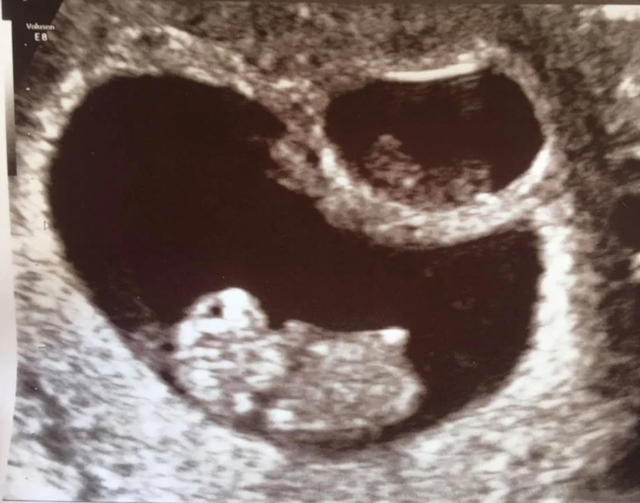

从彩超单子上可以看出,两个胎儿一大一小,并且做胎心监护的时候,只能听见一个宝宝的心跳了,对此,这位孕妈很伤心。于是跑到其他医院进行检查,结果得出的结论出奇的一致。

最令人惊奇的是,孕13周,女子再次进行孕检的时候,腹中只剩下一个孩子的影像了,其中的一个居然被吸收掉了。